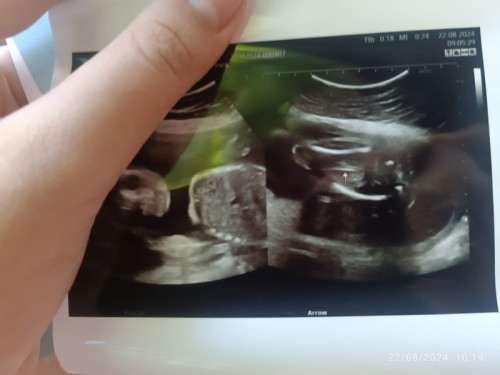

น้องเพศอะไรหมอไม่บอกเลยคะแม่ๆ 😭😭5เดือนจะ6เดือนแล้ว

เพศผู้หญิงนะคะเราเห็นเหมือนกลีบ